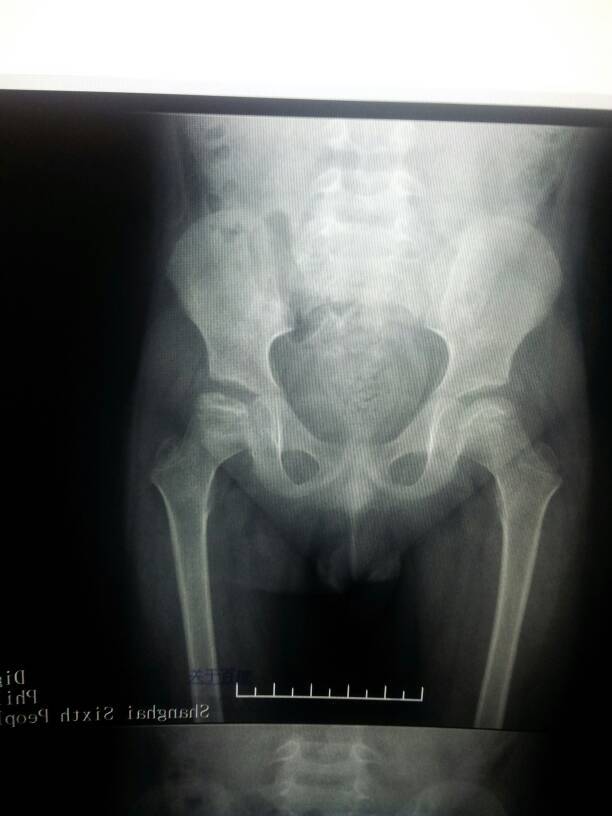

儿童股骨头坏死保守治疗,不负重一年了!男孩,五岁三个月,外展可以,没有疼痛感,这是近期拍的片子,麻烦接触过此类型病的医生帮帮忙看看,十分焦急!!!

病情还是很严重的。好在是年龄还小,6岁以下,可以选择的导查治疗方法也有很多(手术治疗、非手术治疗都有很多方案),具体治疗方法的选择需要乔厘菜详细全面的检查,不能一概而论。我对此病的治疗经验还不足。给你提供一条线索吧,国内对怨惑这个病搞深入研究的专家,首推刘正全教授,他任职于重庆医科大学儿童医院。最后,祝小伙子好运、早日恢复健康。